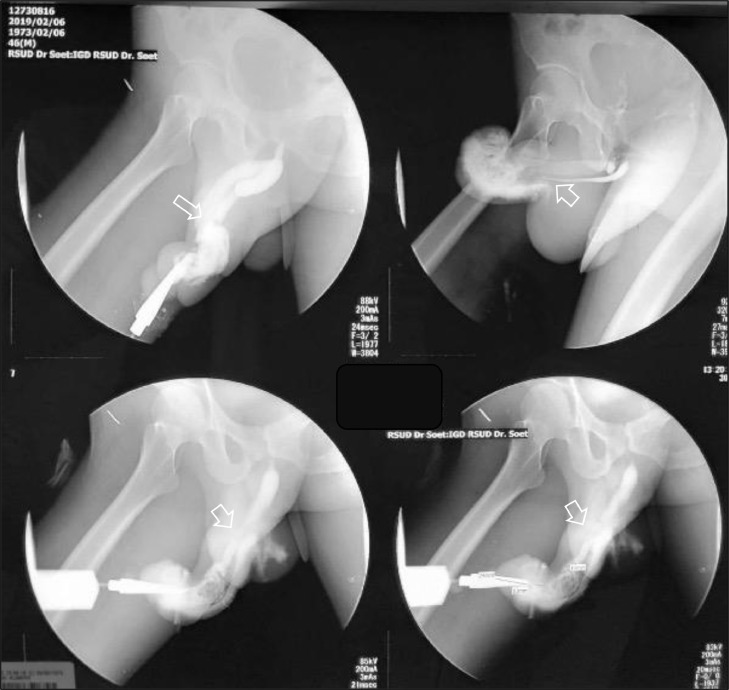

Fig. 3.

Urethrography with retrograde urethrogram fluoroscopy contrast injected into the penile orifice examination: the contrast leakage, measuring 2.4 cm in length, was evident at around 2.9 cm proximal to the external urethral orifice. The contrast filled the right cavernous body and proximal urethra at the cavernous, bulbous, membranous and prostatic parts, and the bladder. Conclusion: Urethral rupture at the cavernous part at approximately 2.4 cm from the external urethral orifice and ruptured right cavernous body.